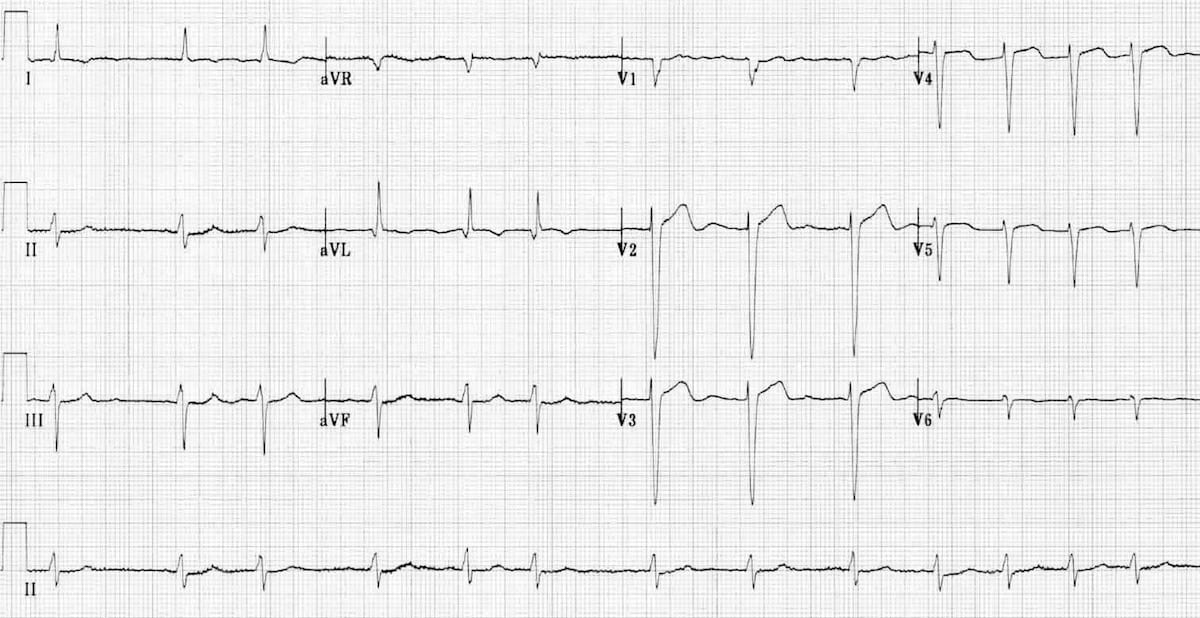

ECG Examples

Remember, the Thumb rule is helpful to work out the cardiac axis, by just looking at 2 leads:

-

👍 Lead I up (+ve), 👍 aVF up (+ve) → normal axis

-

👍 Lead I up (+ve), 👎 aVF down (-ve) → left axis deviation

-

👎 Lead I down (-ve), 👍 aVF up (+ve) → right axis deviation

- 👎 Lead I down (-ve), 👎 aVF down (-ve) → extreme (north-west) axis deviation

This ECG shows left axis deviation. Applying the thumb rule: lead I is up (+ve) and lead aVF is down (-ve). The left axis deviation is secondary to left ventricular hypertrophy.

© Life in the Fast Lane. Licensed under CC BY-NC 4.0

This ECG shows right axis deviation. Applying the thumb rule: lead I is down (-ve) and lead aVF is up (+ve). The right axis deviation is secondary to right ventricular hypertrophy (from cor pulmonale).

https://litfl.com/top-100-ecg-cases/

© Life in the Fast Lane. Licensed under CC BY-NC 4.0